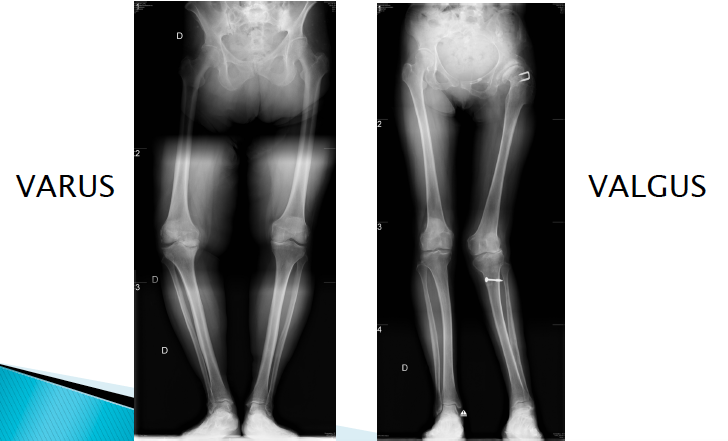

Quels types de déformation d’alignement peut causer l’arthrose?

Une déformation en varus (90%) ou en valgus

Des ostéotomies sont indiquées s’il y a présence d’un mal alignement articulaire. L’avantage principal de l’ostéotomie est la préservation de l’articulation. Ceci peut permettre de retarder l’arthroplastie, surtout chez les jeunes patients.

L’ostéotomie permet un réalignement osseux, qui aura pour effet de mieux répartir la charge mécanique sur une surface articulaire saine, tout en préservant le stock osseux. On va couper un petit triangle dans l’os pour permettre de choisir ou s’appuiera la charge mécanique

Elle est principalement pratiquée au niveau du tibia proximal dans les arthroses varisantes du genou.